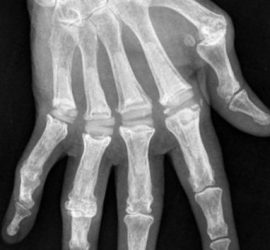

A polidactilia na Mesa Redonda de Malformações congénitas da Mão do Congresso Ibero-Americano 2017

A polidactilia, 2ª deformidade congénita mais frequente na Mão foi um dos temas apresentados na Mesa Redonda de Malformações congénitas da Mão, ocorrida no XI Congresso Ibero-Americano de Cirurgia da Mão que se realizou na Costa Rica nos dias 27 a 29 de Abril de 2017 Polidactilia é um termo […]

Melhor Poster no 5º Congresso Nacional e XXII Jornadas de Ortopedia Infantil

O Poster “Transferência de dedo do pé para a mão para reconstrução digital em malformação congénita” foi distinguido com o premio de melhor Poster no 5º Congresso Nacional e XXII Jornadas de Ortopedia Infantil, que se realizou em Lisboa nos dias 24 e 25 de março de 2017. Autores: CLÁUDIA […]

Anomalias Congénitas do Polegar, Conferencia apresentada no 8ª Congresso Grupo Estudio Patología Extremidad Superior (GEPES) – Viana do Castelo, Maio de 2015

Deformidades Congénitas do Polegar: Tema da Conferencia de Encerramento do VIII CONGRESSO GEPES Nesta Conferencia descrevi as Deformidades Congénitas mais frequentes do Polegar, com especial atenção para a Hipoplasia do Polegar, as Polidactilias (duplicação) do Polegar, Desvios Axiais, Anomalias Tendinosas, Polegar em Mola Congénito. O envolvimento do polegar noutras Deformidades […]

10º Simposium mundial de deformidades congénitas da mão e Membro Superior, Roterdão – Maio de 2015

Realizou-se em Roterdão, 7 a 9 de Maio de 2015. Apresentou o Tema Atipycal Radial Club Hand Summary: The goal of this paper is to present our casuistic of radial club hand with atypical features We have treated 14 child with radial club hand. Between of them we have two cases […]

As Sindactilias no VII Congreso Grupo Estudio Patología Extremidad Superior (GEPES) – La Corunha, 17 e 18 de Outubro de 2014

Palestrante convidado para integrar mesa-redonda sobre malformações congénitas da mão durante o sétimo Congresso do GEPES (Grupo de EstudIos de Patologia de la Extremidad Superior) a decorrer na Corunha em 17 e 18 de outubro de 2014. O tema da sua apresentação são as Sindactilias, trabalho baseado na sua experiência […]